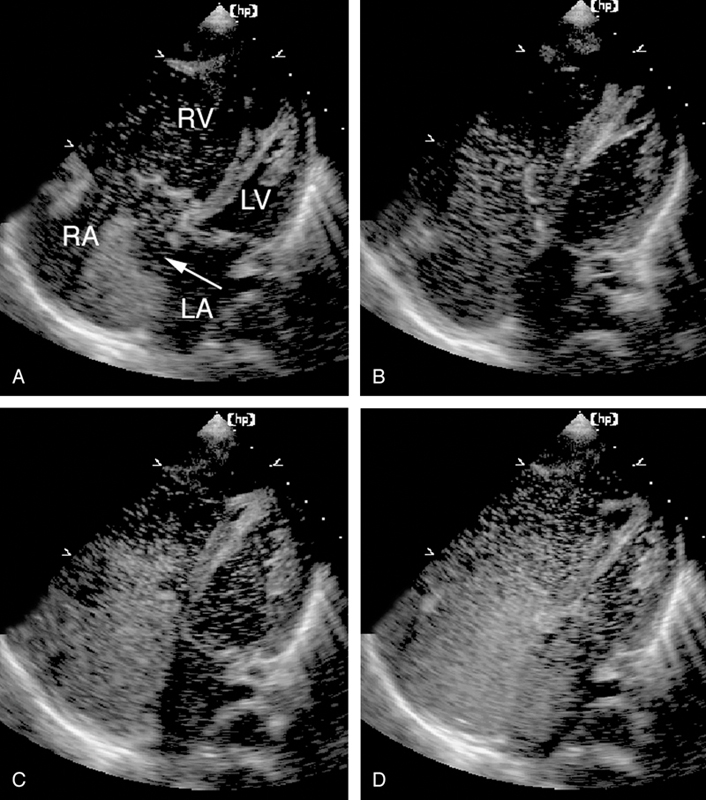

فحوصات تشخيصية لبعض امراض القلب والشرايين التاجية